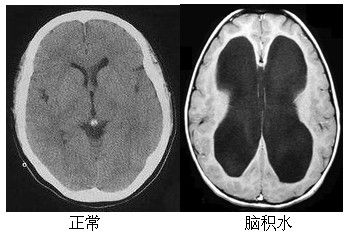

脑积水临床症状并不一致,与病理变化出现的年龄、病理的轻重、病程的长短有关。胎儿先天性脑积水多致死胎,出生以后脑积水可能在任何年龄出现,多数于生后6个月出现。年龄小的患者颅缝未接合,头颅容易扩大,故颅内压增高的症状较少。那么,脑积水有哪些临床表现呢?

脑积水是神经外科常见病和多发病,发病机制、临床表现、分类方法及治疗方法多种多样。目前临床上脑积水的治疗方法也较多,手术治疗方法仍为主要的方式,常用的手术治疗方法是:“CRAS机器人“脑外手术定位系统+神经调控术。